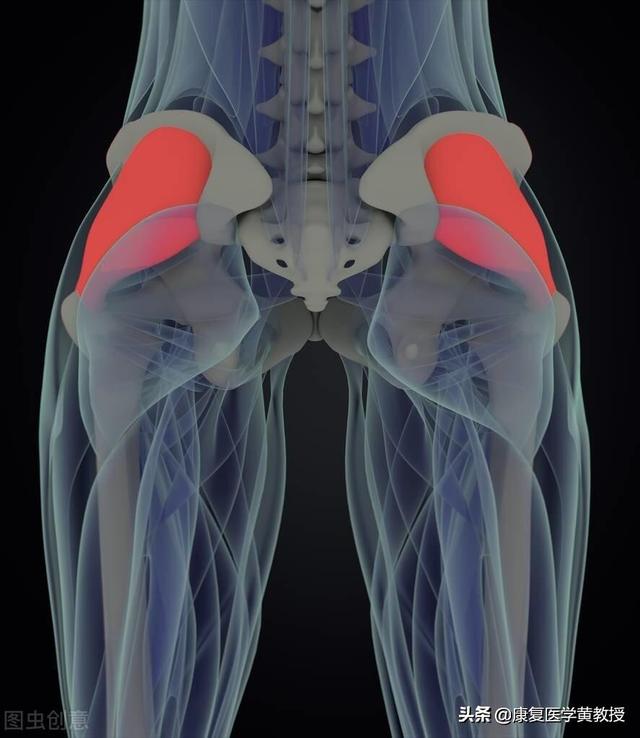

筋骨格系(頸椎を含む)の動作は、どれも単独では起こりえない。中枢神経系、末梢神経系、筋・筋膜・骨格系、感覚受容器系、循環器系が連携して働く。単純な頭の回転やうなずきを行うには、システムのサブシステムのどれかに問題があると、動作の実行に影響が出る。

この頸椎は動きたがっていて、すべては筋肉が主導権を握っている。

もともと筋肉は互いに独立しており、それぞれが独自の方向に力を発揮していた。

しかし、悪い姿勢が長く続き、常に一方向に力がかかっていると、その方向の筋肉が常に圧迫され、時間の経過とともに癒着が生じる。

筋肉同士がくっつけばくっつくほど、その力は大きくなり、頸椎を強く引っ張る。頸椎が変形すればするほど、より多くの筋肉が一緒に圧迫される。悪循環である!

ミニニードルナイフの原理は単純で、癒着した組織をほぐして分離し、頸椎にかかる筋肉の引っ張りを軽減し、頸椎の隣接組織への圧迫を和らげる。